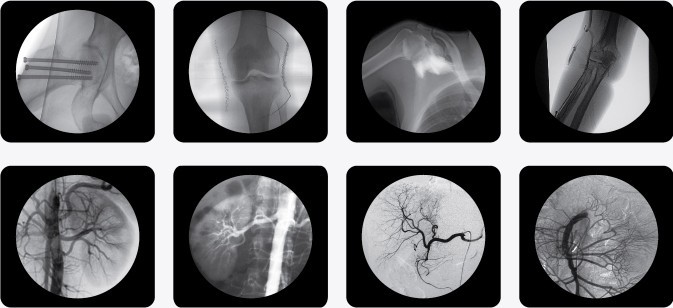

PLX7000B高頻移動式C型臂X射線機(C型臂X光機)

一、C型臂X光機PLX7000B的用途

廣泛應用于 介入科、骨科、外科、矯形外科、泌尿外科、脊柱外科、腹部外科、疼痛科、心臟科、消化科、婦科及手術室等。

三、C型臂X光機PLX7000B數字高清影像,支持您做出精確診斷

·全數字化百萬像素影像采集系統,優化設計和配置,為您提供高分辨率、高灰階圖像,支持您做出精確診斷。

·專業的圖像處理系統,具備非凡處理能力,確保您的所想即您的所得

1、內置先進圖像自動優化處理、增強模塊,實時顯示自動優化后的清晰臨床影像。

2、專業的影像處理工作站具備窗寬窗位調節、自動伽瑪校正、興趣點、反相、降噪、平滑、銳化等豐富且強大影像處理功能,帶給您更強大的診斷信心。

·專用高清醫用液晶顯示系統,呈獻給您高亮度、高對比度的臨床圖像;對比自然,有益于診斷的圖像細節顯示更加清晰、層次更加豐富